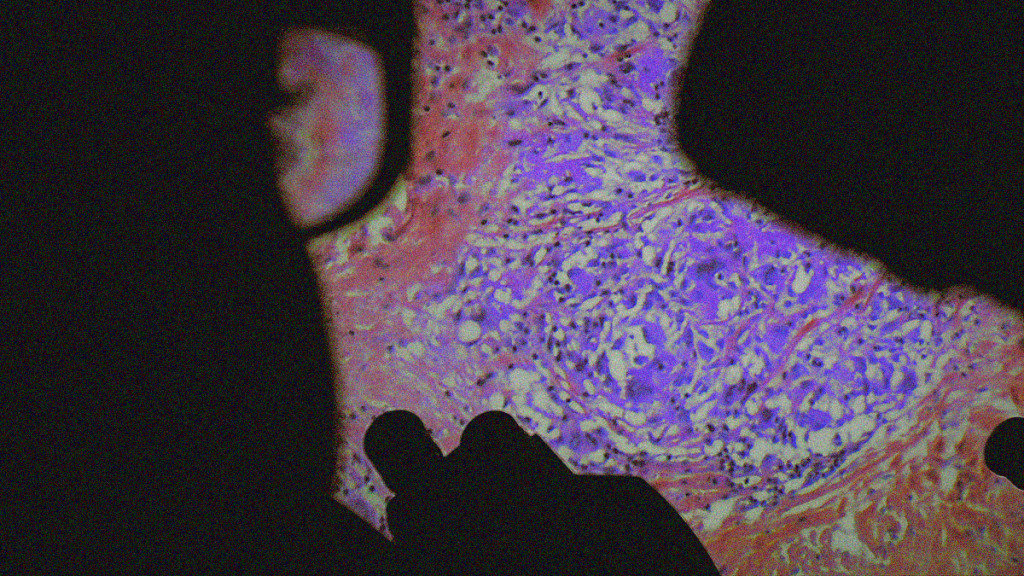

REVIEW: De Humani Corporis Fabrica [2023]